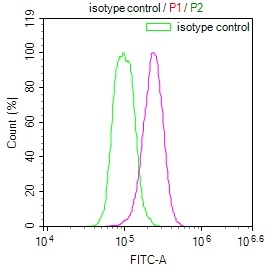

圖片:

The image on the left is immunohistochemistry of paraffin-embedded Human ovarian cancer tissue using CSB-PA969280(IRS2 Antibody) at dilution 1/100, on the right is treated with synthetic peptide. (Original magnification: ×200)